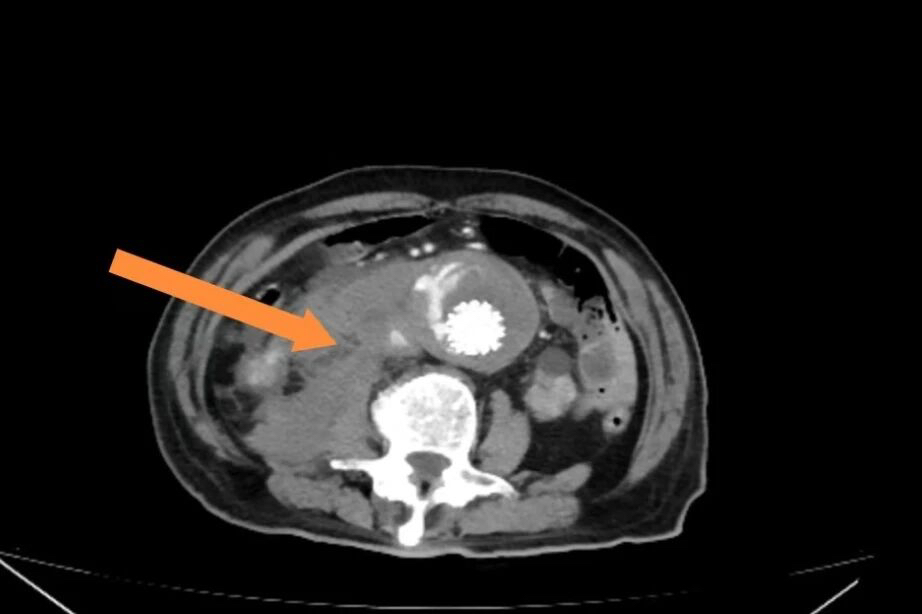

“立即做腹部 CTA!” 急诊科医生第一时间下达指令,护士已推着检查床冲向影像科。清晰的影像在屏幕上展开:多年前植入的腹主动脉支架分支出现脱落,造影剂正从支架与血管的间隙汹涌溢出,在腹膜后积成血肿。泛着白光的 “阴影”,正是腹主动脉瘤濒临破裂的信号。